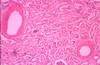

What is this?

ATN

key feature here: cortical pallow (esp. in ischemic subtype)